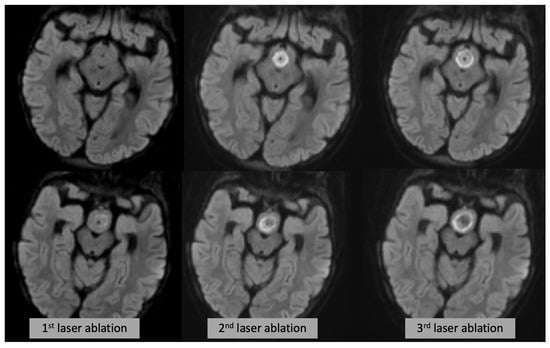

Figure 4. Axial DWI (each row showing a different slice/level) at the time of the first (left), second (middle) and third (right) laser ablation, showing progressive expansion of the DWI changes.